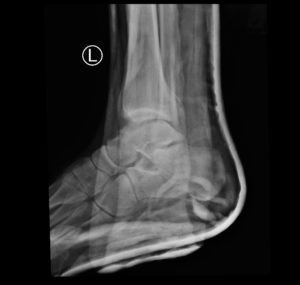

Subtalar dislocation is an unusual form of joint injury from high-energy trauma or athletic injuries. This case report describes a 22-year-old male who presented to the emergency department with left ankle pain after falling from his bicycle. Examination revealed significant deformity of the left foot and ankle. The foot pointed medially, and the bottom portions of the tibia and fibula were visible with the overlying skin intact. Radiographs confirmed left medial subtalar dislocation. There was no neurovascular compromise of the foot. The dislocation was successfully reduced under procedural sedation and the patient’s left leg was placed in a splint. He underwent post-reduction imaging and was instructed to remain non-weight-bearing and to follow up with orthopedics to discuss further management. The purpose of this report is to describe a case of a closed, medial subtalar dislocation and the approach to management.